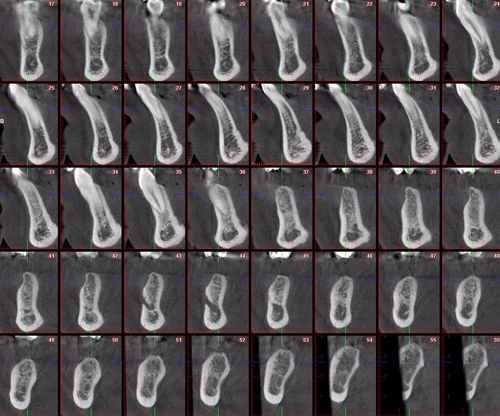

Palabras Clave: ELG: Estereolitográfico OH: Oclusión Habitual ORC: Oclusión en Relación Céntrica Paciente de 35 años de edad ,sexo masculino que lo derivan para implantar el tercer cuadrante. A la auscultación presenta ruidos articulares de tipo chasquido que remiten temporalmente luego de limitación de apertura bucal y maniobras quinesiológicas distractoras. También se observan recidivas de caries en algunos empastes y falta de disclusión canina de ambos lados. Se estudia el caso desde un punto de vista clínico, scanografico mediante Dentascan y tridimensional mediante montaje en articulador. A partir del scanner se obtienen datos para confeccionar modelo estereolitográfico (ELG),operar en el y construir férula quirúrgica dento-muco soportada. Habitualmente se procede directamente a implantar, dado que ese era el requerimiento del profesional derivante y el deseo del enfermo. Sin embargo, esa actitud enmascararía otro tipo de problemas que la boca presenta. Se consulta al odontólogo derivante, y coincide con mi opinión acerca de que si solo se lo implanta, sin corregir la posición mandibular, la situación de las ATMs, los empastes sin anatomía y la falta de disclusiones, el resultado final no será el deseado y su eficacia masticatoria no funcionará optimamente. Consultado el paciente coincide y acepta ese concepto y entonces procedemos a confeccionar un Jig de Lucia a partir del montaje de estudio, y lo dejamos puesto en boca toda la noche anterior a la consulta, para proceder a realizar un ajuste oclusal al día siguiente sin engramas anteriores, lo que facilita no tener que relajar nuevamente con laminillas de Long. En esta etapa pierde el implante correspondiente a la pieza 4.7 que traía en boca. Estabilizado el sistema, procedemos a la parte quirúrgica, comenzando por instalar la férula, retirar opérculos gingivales mediante bisturí circular, fresado óseo e instalación de implantes ,toma de impresión a cubeta fenestrada (pegando con metacrilato sin cambios dimensionales, los transfers a la cubeta especialmente diseñada.(1º método de pasividad protética utilizado), e instalación de tornillos de cicatrización. Inmediatamente de retirada la cubeta de boca y colocadas las réplicas de los implantes, procedemos a ferulizar los “ápices” de las réplicas para que no sufran movimientos durante el llenado de la impresión.(2º método de pasividad protética utilizado). Controlamos radiograficamente Tres meses después, procedemos a tomar nuevos registros de arco facial, registros intermaxilares en Oclusión en Relación céntrica, montaje de los modelos obtenidos intra operatoriamente y confección de un conjunto de cuatro coronas provisionales de metacrilato en el sector implantado y las correspondientes al maxilar superior. Verificada la perfecta función de todos los componentes, ausencia de todo tipo de síntoma y comprobada la paz en todo el sistema, procedemos tiempo después a confeccionar las fundas definitivas, que constituyen el “cerrojo” de la dinámica del mismo. Por último, corroboramos la oclusión fundamentalmente en lo que hace a la: